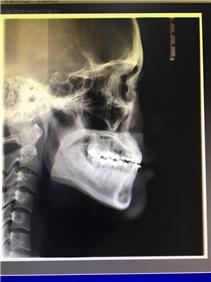

최종적으로 엑스레이를 한번 찍어서 확인을 해주셨어요!

최근에는 옥니가 안되게끔 앞니를 충분히 앞으로 꺼냈는데,

그러면서도 각도는 돌출입이 되지 않도록 조정해주셨어요!

원장님께서는

아주 교정이 잘되었다고,

제가 노란색으로 표시한 저 각도도 충분히 나와있어서 좋다고 하셨어요!